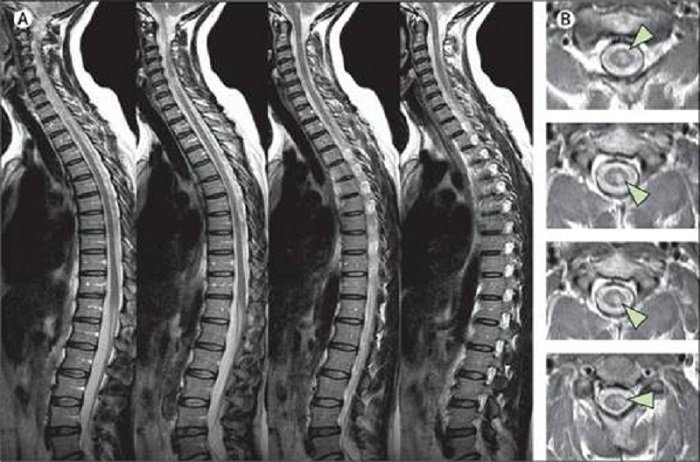

Khác với chụp cắt lớp vi tính, chụp cộng hưởng từ cột sống thắt lưng có thể phát hiện nhiều tình trạng, bệnh lý khác nhau của đoạn cột sống thắt lưng, bao gồm các vấn đề về xương (đốt sống), các mô mềm (như tủy sống), dây thần kinh và đĩa đệm.

MRI đôi khi được thực hiện để đánh giá cấu trúc giải phẫu của cột sống thắt lưng, giúp lập ra các kế hoạch phẫu thuật cột sống hoặc theo dõi những thay đổi ở cột sống sau khi phẫu thuật. Ví dụ, chụp cộng hưởng từ cột sống thắt lưng có thể tìm thấy chứng hẹp ống sống, đoạn chứa tủy sống bị thu hẹp bất thường, và cần phải phẫu thuật để giải phóng chỗ hẹp.

Bên cạnh đó, chụp cộng hưởng từ cột sống thắt lưng cũng có thể đánh giá các đĩa đệm về cấu trúc và vị trí, có Thoát vị đĩa đệm chèn vào tủy sống hoặc dây thần kinh hay không.

Ngoài ra, một ưu điểm của chụp cộng hưởng từ cột sống thắt lưng là hữu ích trong việc đánh giá các triệu chứng như đau lưng dưới, đau chân, tê, Ngứa ran hoặc yếu chi cũng như các vấn đề về kiểm soát bàng quang và ruột. Đồng thời, phim chụp cộng hưởng từ cũng có thể giúp chẩn đoán khối u, chảy máu, sưng viêm, nhiễm trùng ở đốt sống hoặc các mô xung quanh.

Những bệnh lý thường gặp trên phim chụp cộng hưởng từ cột sống thắt lưng thường liên quan với các cấu trúc xương khớp, đĩa đệm, dây chằng và thần kinh. Trong đó, các bệnh lý cấp tính của thần kinh là đặc biệt quan trọng. Qua đó, bằng cách kết hợp với các bằng chứng lâm sàng, bác sĩ sẽ đưa ra những quyết định can thiệp tức thời, nhằm hạn chế các tổn thương ở mức tối thiểu cũng như phòng tránh các di chứng về sau.

Đối với các bệnh lý xương khớp mạn tính, kết quả chụp cộng hưởng từ cột sống thắt lưng như là một yếu tố góp phần chẩn đoán và cân nhắc quyết định can thiệp ngoại khoa, tùy vào bệnh cảnh lâm sàng với mục tiêu đem đến lợi ích cao nhất, khả năng hồi phục cho người bệnh.

Tóm lại, chụp cộng hưởng từ cột sống thắt lưng không tiêm thuốc đối quang từ là một công cụ hình ảnh học cao cấp để khảo sát các cấu trúc tại khu vực này. Kết quả chụp không chỉ giúp chẩn đoán bệnh mà còn định hướng điều trị, góp phần quyết định cấp thời trong các tình huống nguy kịch ảnh hưởng đến thần kinh, bảo tồn chức năng cho người bệnh.